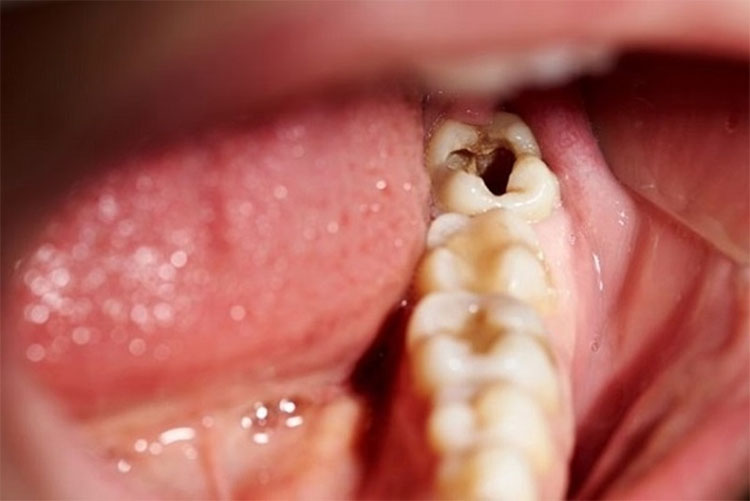

Khi vi khuẩn xâm nhập, tiếp xúc đồng thời tấn công vào bên trong cấu trúc của răng, làm cho bề mặt răng bị tổn thương, trên răng hay xung quanh có thấy những chỗ sâu nhỏ li ti gọi là sâu răng. Khi đó, người bệnh sẽ có cảm giác đau, khó chịu.

Khi vi khuẩn tấn công vào cấu trúc răng, phá hủy men răng, hình thành các lỗ sâu đồng thời gây ra chứng hôi miệng. Bên cạnh đó, những lỗ sâu trên răng cũng là điều kiện thuận lợi để thức ăn tích tụ lại, vi khuẩn sinh sôi và phát triển tại đó. Những lỗ sâu này là nguyên nhân khiến hơi thở có mùi hôi.

Khi bị sâu răng, bạn sẽ thấy những vết chấm vàng hay đen trên thân răng, mặt trong của răng xuất hiện những đốm màu đen, mắt thường có thể nhìn thấy được. Nếu những chấm đen lan rộng theo rãnh, gờ sẽ làm thay đổi màu sắc của răng, lâu dần sẽ có cảm giác đau trong răng. Nếu bị nặng, triệu chứng này sẽ ảnh hưởng không tốt đến quá trình tiêu hóa của bạn.